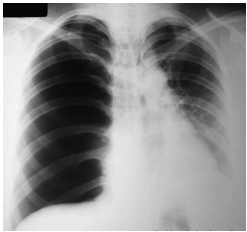

Analisar o seguinte Raio X de tórax de um paciente com história de ferimento por arma branca em tórax à direita, dando entrada na emergência com dor torácica, dispneia intensa, hipotensão e confusão mental:

Assinalar a alternativa cuja conduta é preconizada para esse momento: